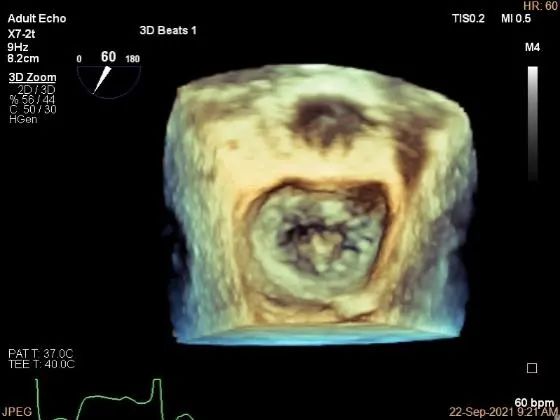

术中超声

3D:P1区脱垂并腱索断裂,Width:11.4mm

3D-color:重度MR,4级

MVA:7.8cm²,平均跨瓣压差:1mmHg

夹子夹闭后,未见明确残余分流

3d确认夹子位置在P1区

3d-color确认残余分流情况

评估二尖瓣瓣口平均跨瓣压差:1mmHg